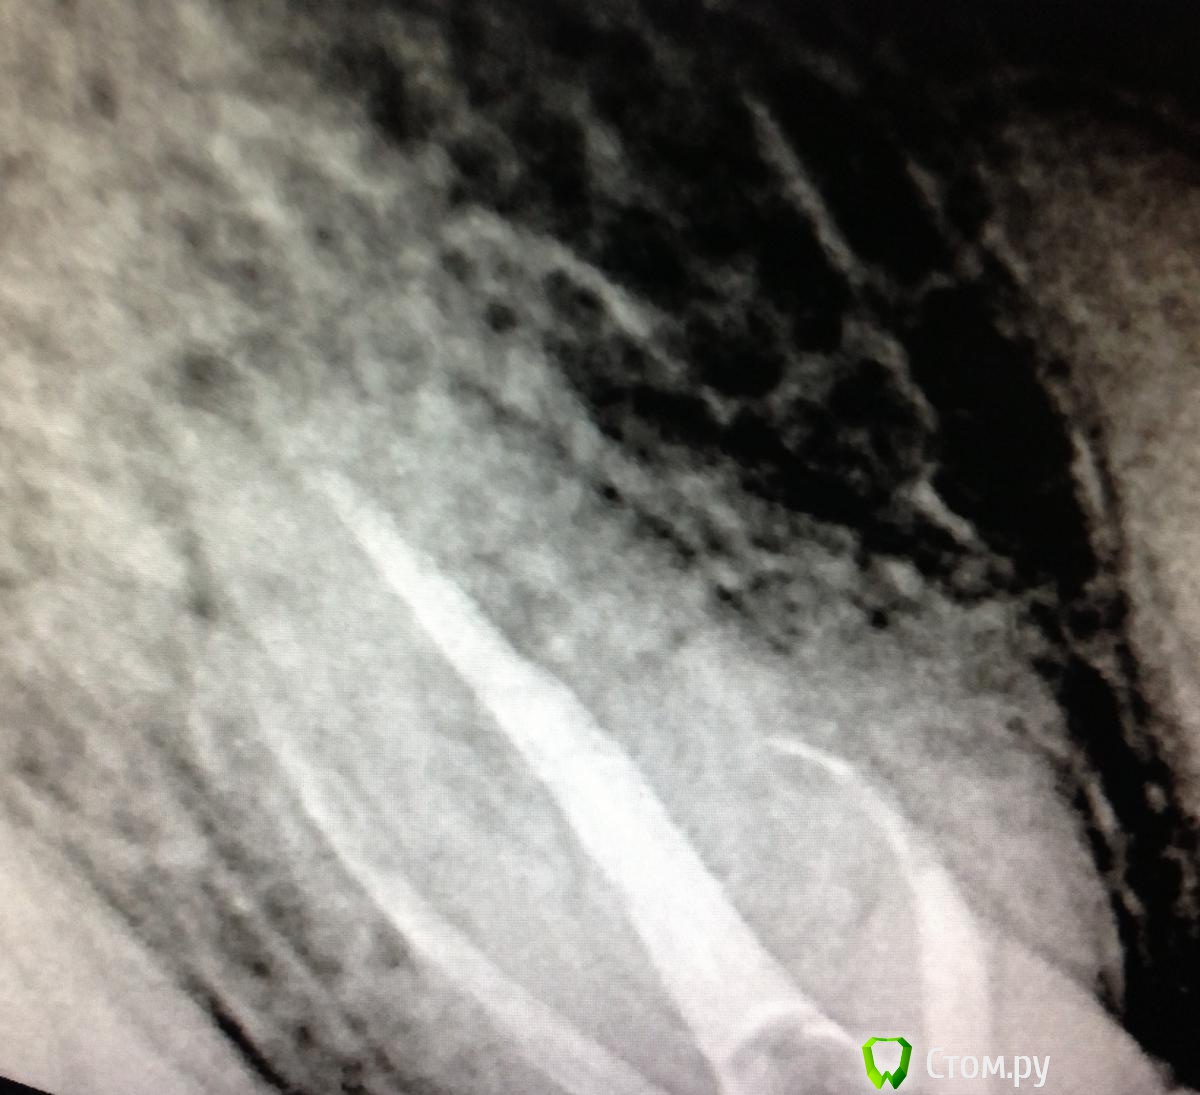

SSTi Опубликовано 19 июля, 2014 Автор Поделиться Опубликовано 19 июля, 2014 Зуб 27. Накрылся новапекс. Работа наощупь. Снимок после временной. Кто сколько каналов видит? 2 посещения искали 3 и 4 каналы. Не нашел Ссылка на комментарий

SSTi Опубликовано 19 июля, 2014 Автор Поделиться Опубликовано 19 июля, 2014 Топография устьев такая Ссылка на комментарий

Kolchanov Опубликовано 20 июля, 2014 Поделиться Опубликовано 20 июля, 2014 А эти сходились? Бывали двухканальные семерки. 1 Ссылка на комментарий

SSTi Опубликовано 20 июля, 2014 Автор Поделиться Опубликовано 20 июля, 2014 Эти не сходились. Два отдельных. Ссылка на комментарий